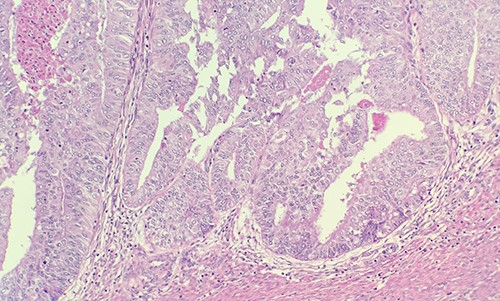

Patient was admitted for hysterectomy for endometrial carcinoma. There is a mass lesion measuring 4.3 × 4 cm located in right ovary indicating metastatic from uterine endometrial primary on image study. Microscopic examination of endometrial reveals endometrial adenocarcinoma, endometrioid type, FIGO Grade 2 (Fig. 1). Microscopic examination of ovary shows solid growth of tumor cells with angulated pale nuclei and nuclei grooves (Fig. 2). Tumor cells are positive for CD56, CD99, Calretinin (Fig. 3) and inhibin, combined with morphological features; this immunoprofile supports the diagnosis of granulosa cell tumor, adult type.

Microscopic examination of ovary shows solid growth of tumor cells with angulated pale nuclei and nuclei grooves (H&E ×40).